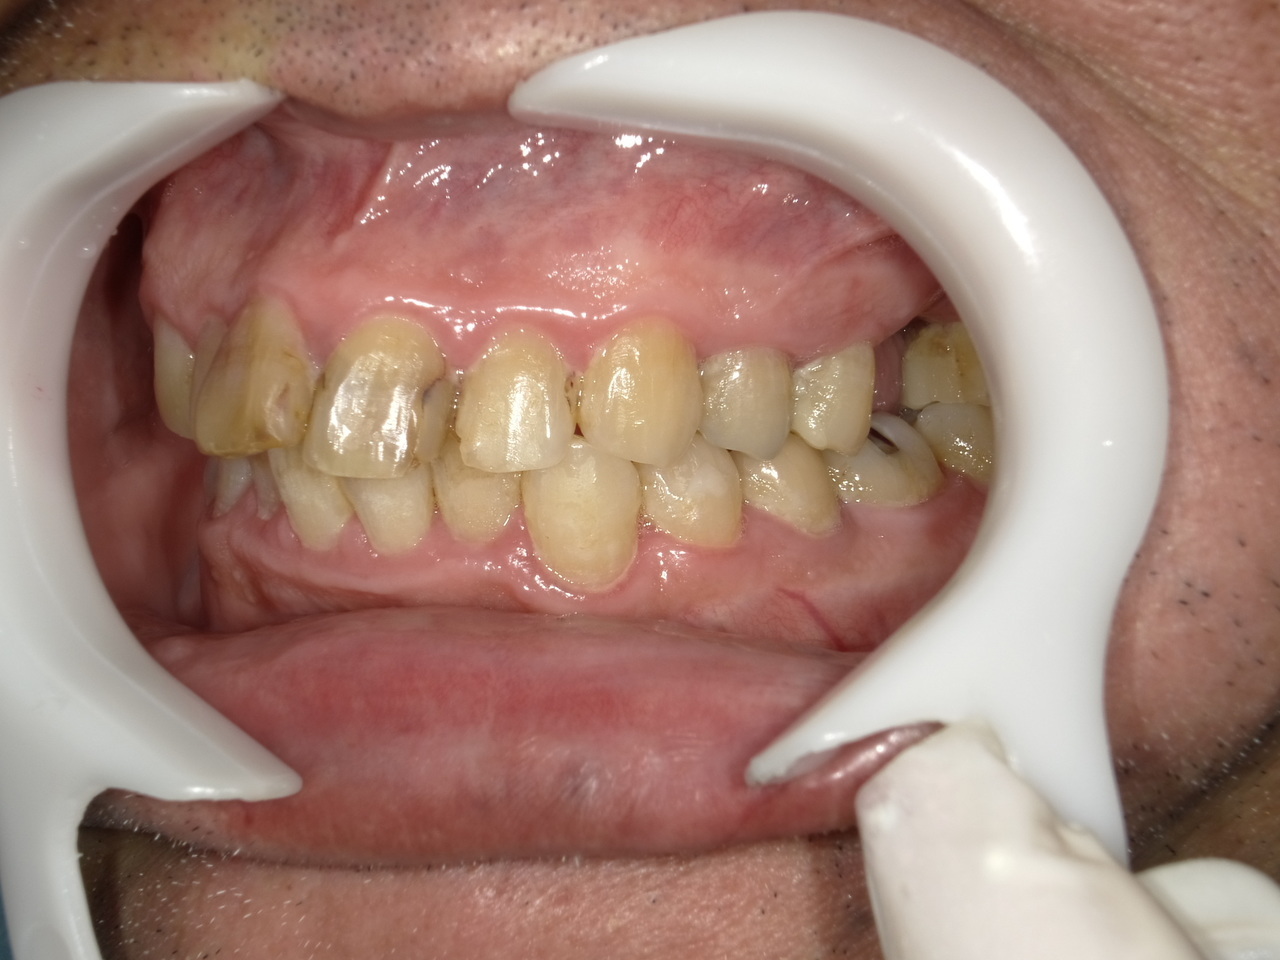

5.左上4番のインプラント抜歯即時埋入、左上6番の上顎既存骨1から2mmのグラフトレスサイナスリフト、左下56の大幅な骨欠損により、下顎神経の損傷を回避するために、ショートインプラントを使用し、左下56にインプラントを埋入し、最終補綴物は、左上456の3ユニットのジルコニアブリッジし、左下56は、ジルコニアの連結冠を装着したケース

Before

枚方市のインプラントの症例

M・I 様 女性 70代

症状としては、左下56は、歯周病で欠損したと考えられるが、かなりの骨欠損をともなっていた。左上456に関しては、動揺が大きく、炎症が起き、排膿、および、歯性上顎洞炎を起こしていた。

治療法としては、動揺がひどくなってきて、炎症の症状もあったため、左上56の抜歯を希望。インプラント治療をその後、希望したため、左上4に関しては抜歯即時埋入。左上6に関しては、既存骨1から2mmでインプラント治療が厳しい状態であったが、グラフトレスサイナスリフトを行い、治療期間5か月はかかるということを説明して、インプラント埋入をおこないました。その後、2か月半後、大幅に骨が欠損している下顎56に対して、ショートインプラントを使用して、下顎神経の損傷を避けて、インプラント埋入を終えています。その後2か月後に光学印象で印象を行い、上顎刺億456歯、3ユニットのジルコニアブリッジを装着。下顎左側56に関しては、骨欠損が大きいため、歯冠長がだいぶ長くなるため、ジルコニアの連結冠を装着して治療を終えた。

治療結果は、上顎6に関しては、既存骨が少なく、厳しい治療ではありましたが、5か月で治療を終え、患者様の負担を最小限に抑えるができたと考えます。(従来のサイナスリフトでは、このようなケースでは1年以上、1年程度の治療期間がかかるか、治療が不可能と言われるケースだと考えます。)また、下顎は骨欠損が大きく、下歯槽管のリスクが起きることが考えられますが、ショートインプラントを使用することで安全に治療を行うことができました。

治療の期間・回数:治療期間5か月(上顎456 3ピースブリッジの治療は5か月(上顎既存骨が2mm程度しかなく、骨結合に時間がかかるケースであったために、5か月の治療期間が必要であった。)(左下56に関しては2か月半で治療を終えています。)治療回数は、13回。

治療の価格:1,474,000円(税込)

治療費の内訳:左上46および左下56のインプラント基本料(フィックスチャー及び手術費用、投薬費用、レントゲン費用、インプラント上部費用(アバットメントおよびジルコニアクラウンの費用用)330000円(税込み)×4本分 1320000円(税込)。左上5ジルコニアポンテック費用88000円(税込)。オプション費用、左上4抜歯即時埋入加算(人工骨費用を含む)+グラフトレスサイナスリフト費用 33000円(税込)、左上6グラフトレスサイナスリフト費用 33000円(税込)

治療のリスクや副作用:手術後に、痛みや腫れ、出血、合併症などを引き起こす可能性があります。噛む感覚がご自身の歯と異なる場合があります。見た目がご自身の歯と異なる場合があります。手術後にメインテナンスを継続しないと、インプラントが抜け落ちる可能性があります。